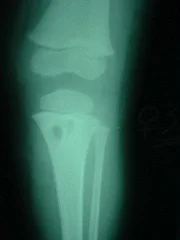

Paciente femenino de 4 años de edad, portadora de HIV, acudió con su representante por mi   consulta, presentando aumento de volumen con signos de rubor y calor en tercio proximal de la pierna izquierda. El laboratorio reporto leucocitosis con elevación de la velocidad de sedimentación globular.

El El estudio radiológico demostró imagen osteolítica en la tibia proximal, procediéndose a la toma de biopsia de la lesión con aguja especial. El diagnóstico histopatológico y bacteriológico fue de osteomielitis crónica por Estafilococo Coagulasa positivo. Fue intervenido quirúrgicamente por el Dr. Alberto A. Martínez Conde,  practicándosele curejate de la lesión con márgenes de resección de aproximadamente

5 mm. Permaneció hospitalizada por 6 semanas con antibiótico terapia parenteral. Recibió tratamiento  por vía oral hasta completar 4 meses. Controlada periódicamente por el Dra. Lisbeth Aurenti (Infectólogo) y el Dr. Alberto A. Martínez Conde. Hasta los momentos 7 años despues, la paciente esta clínicamente curada.